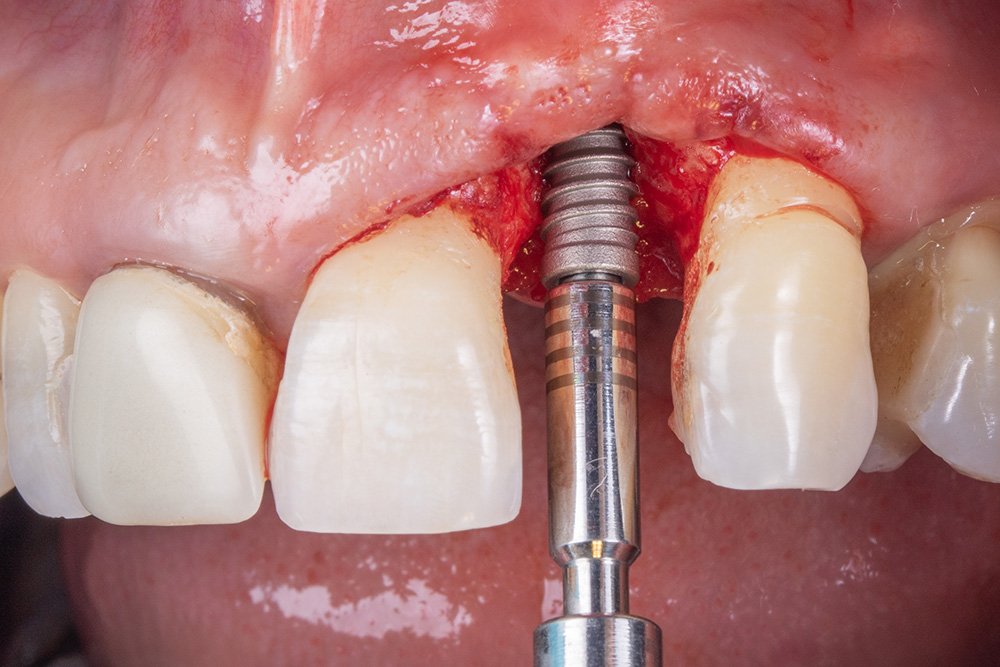

Após realizar a perfuração óssea, utilizou-se o túnel check para mensurar as perfurações e o paralelismo na hora de instalar os implantes.

O implante escolhido foi Cone Morse da Implacil De Bortoli, pois possui certas vantagens comparados aos outros sistemas, como ótimos resultados em relação a manutenção e excelente distribuição de forças fisiológicas ao redor dos tecidos peri-implantares, e mínimo deslocamento do pilar.

Ao final da instalação do implante, é importante mensurar a distância do implante intraósseo, devendo ficar de 2 a 3 mm, considerando a mucosa peri-implantar.